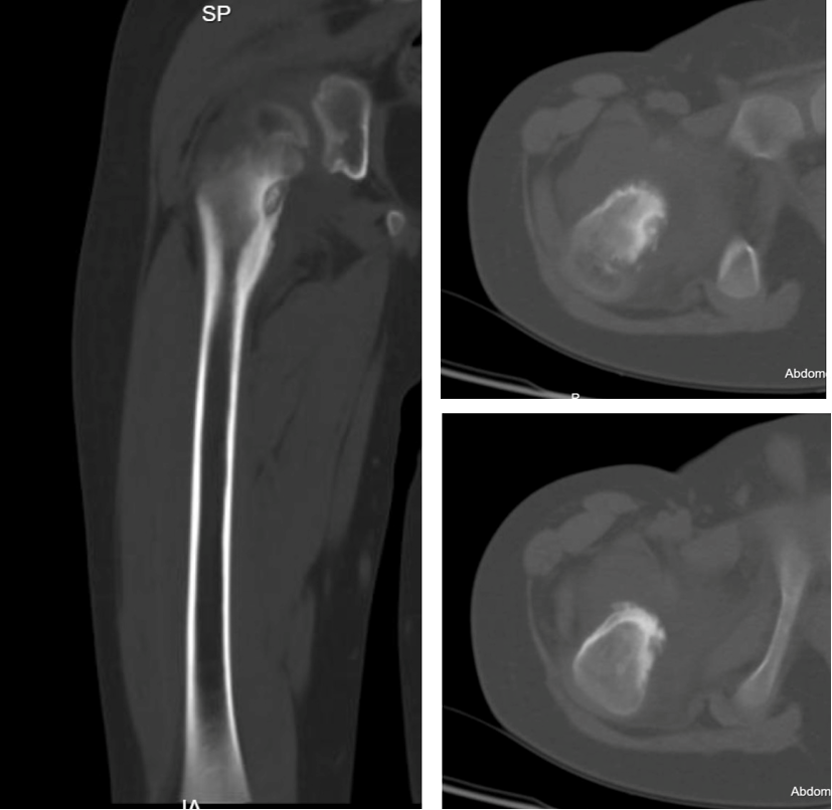

入院后诊断为中心型股骨髓腔骨样骨瘤,本型临床症状不如皮质型明显,部分患者疼痛隐匿,单纯射频消融效果较好。入院后第二天全身麻醉后导航下行左侧股骨病灶射频消融术,选择消融针尺寸为15毫米,消融时间11分30秒。术后第二天患者自诉原有疼痛不适症状缓解90%。术后复查MRI可见骨内明显的椭圆形消融范围,精准对应了23*19毫米的消融范围。

图2:术前CT及MRI见髓腔内松质骨内的瘤巢及周围明显的成骨反应,MRI水肿反应不如骨膜及皮质骨型明显

图5: 术后一个月复诊MRI,显示消融范围与术前计划一致